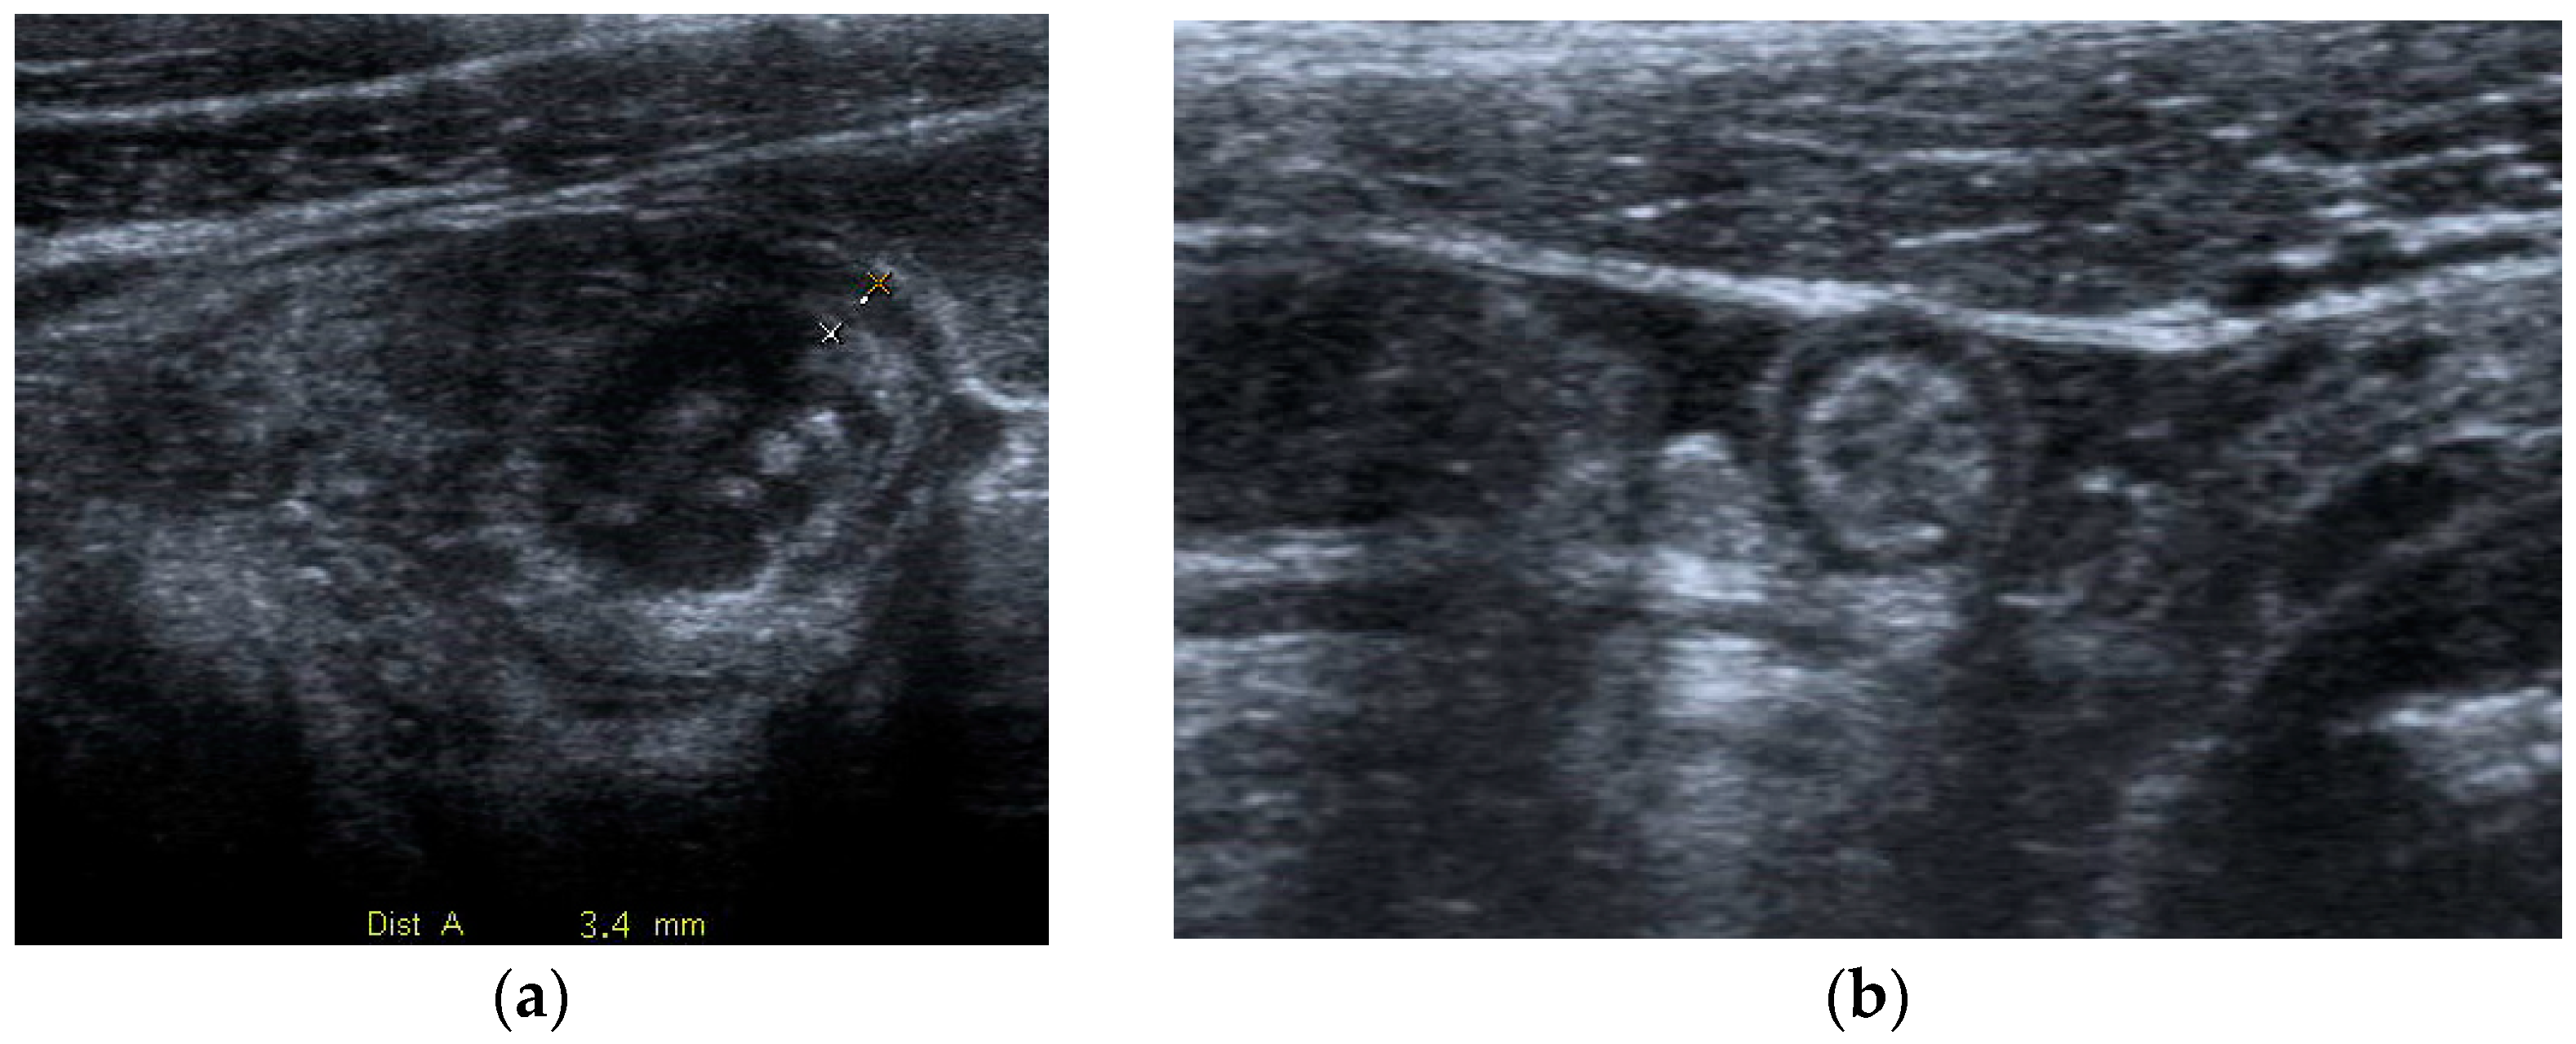

As in non-pregnant patients, AA sonographically appears as a blind-ending, dilated (>6–7 mm in diameter), peristaltic, non-compressible and thick-walled (>2 mm) tubular structure arising from the cecum. Indirect features include fluid effusion in the right iliac fossa and periappendiceal fat stranding (Figure 1).

Figure 1.

Acute appendicitis in a 29-year-old woman with fever and acute abdominal pain. US shows thick-walled (maximum thickness 3.4 mm as indicated in (a)), and dilated tubular structure, containing hyperechoic spots (appendicoliths) (b). Periappendiceal fluid is also depicted.